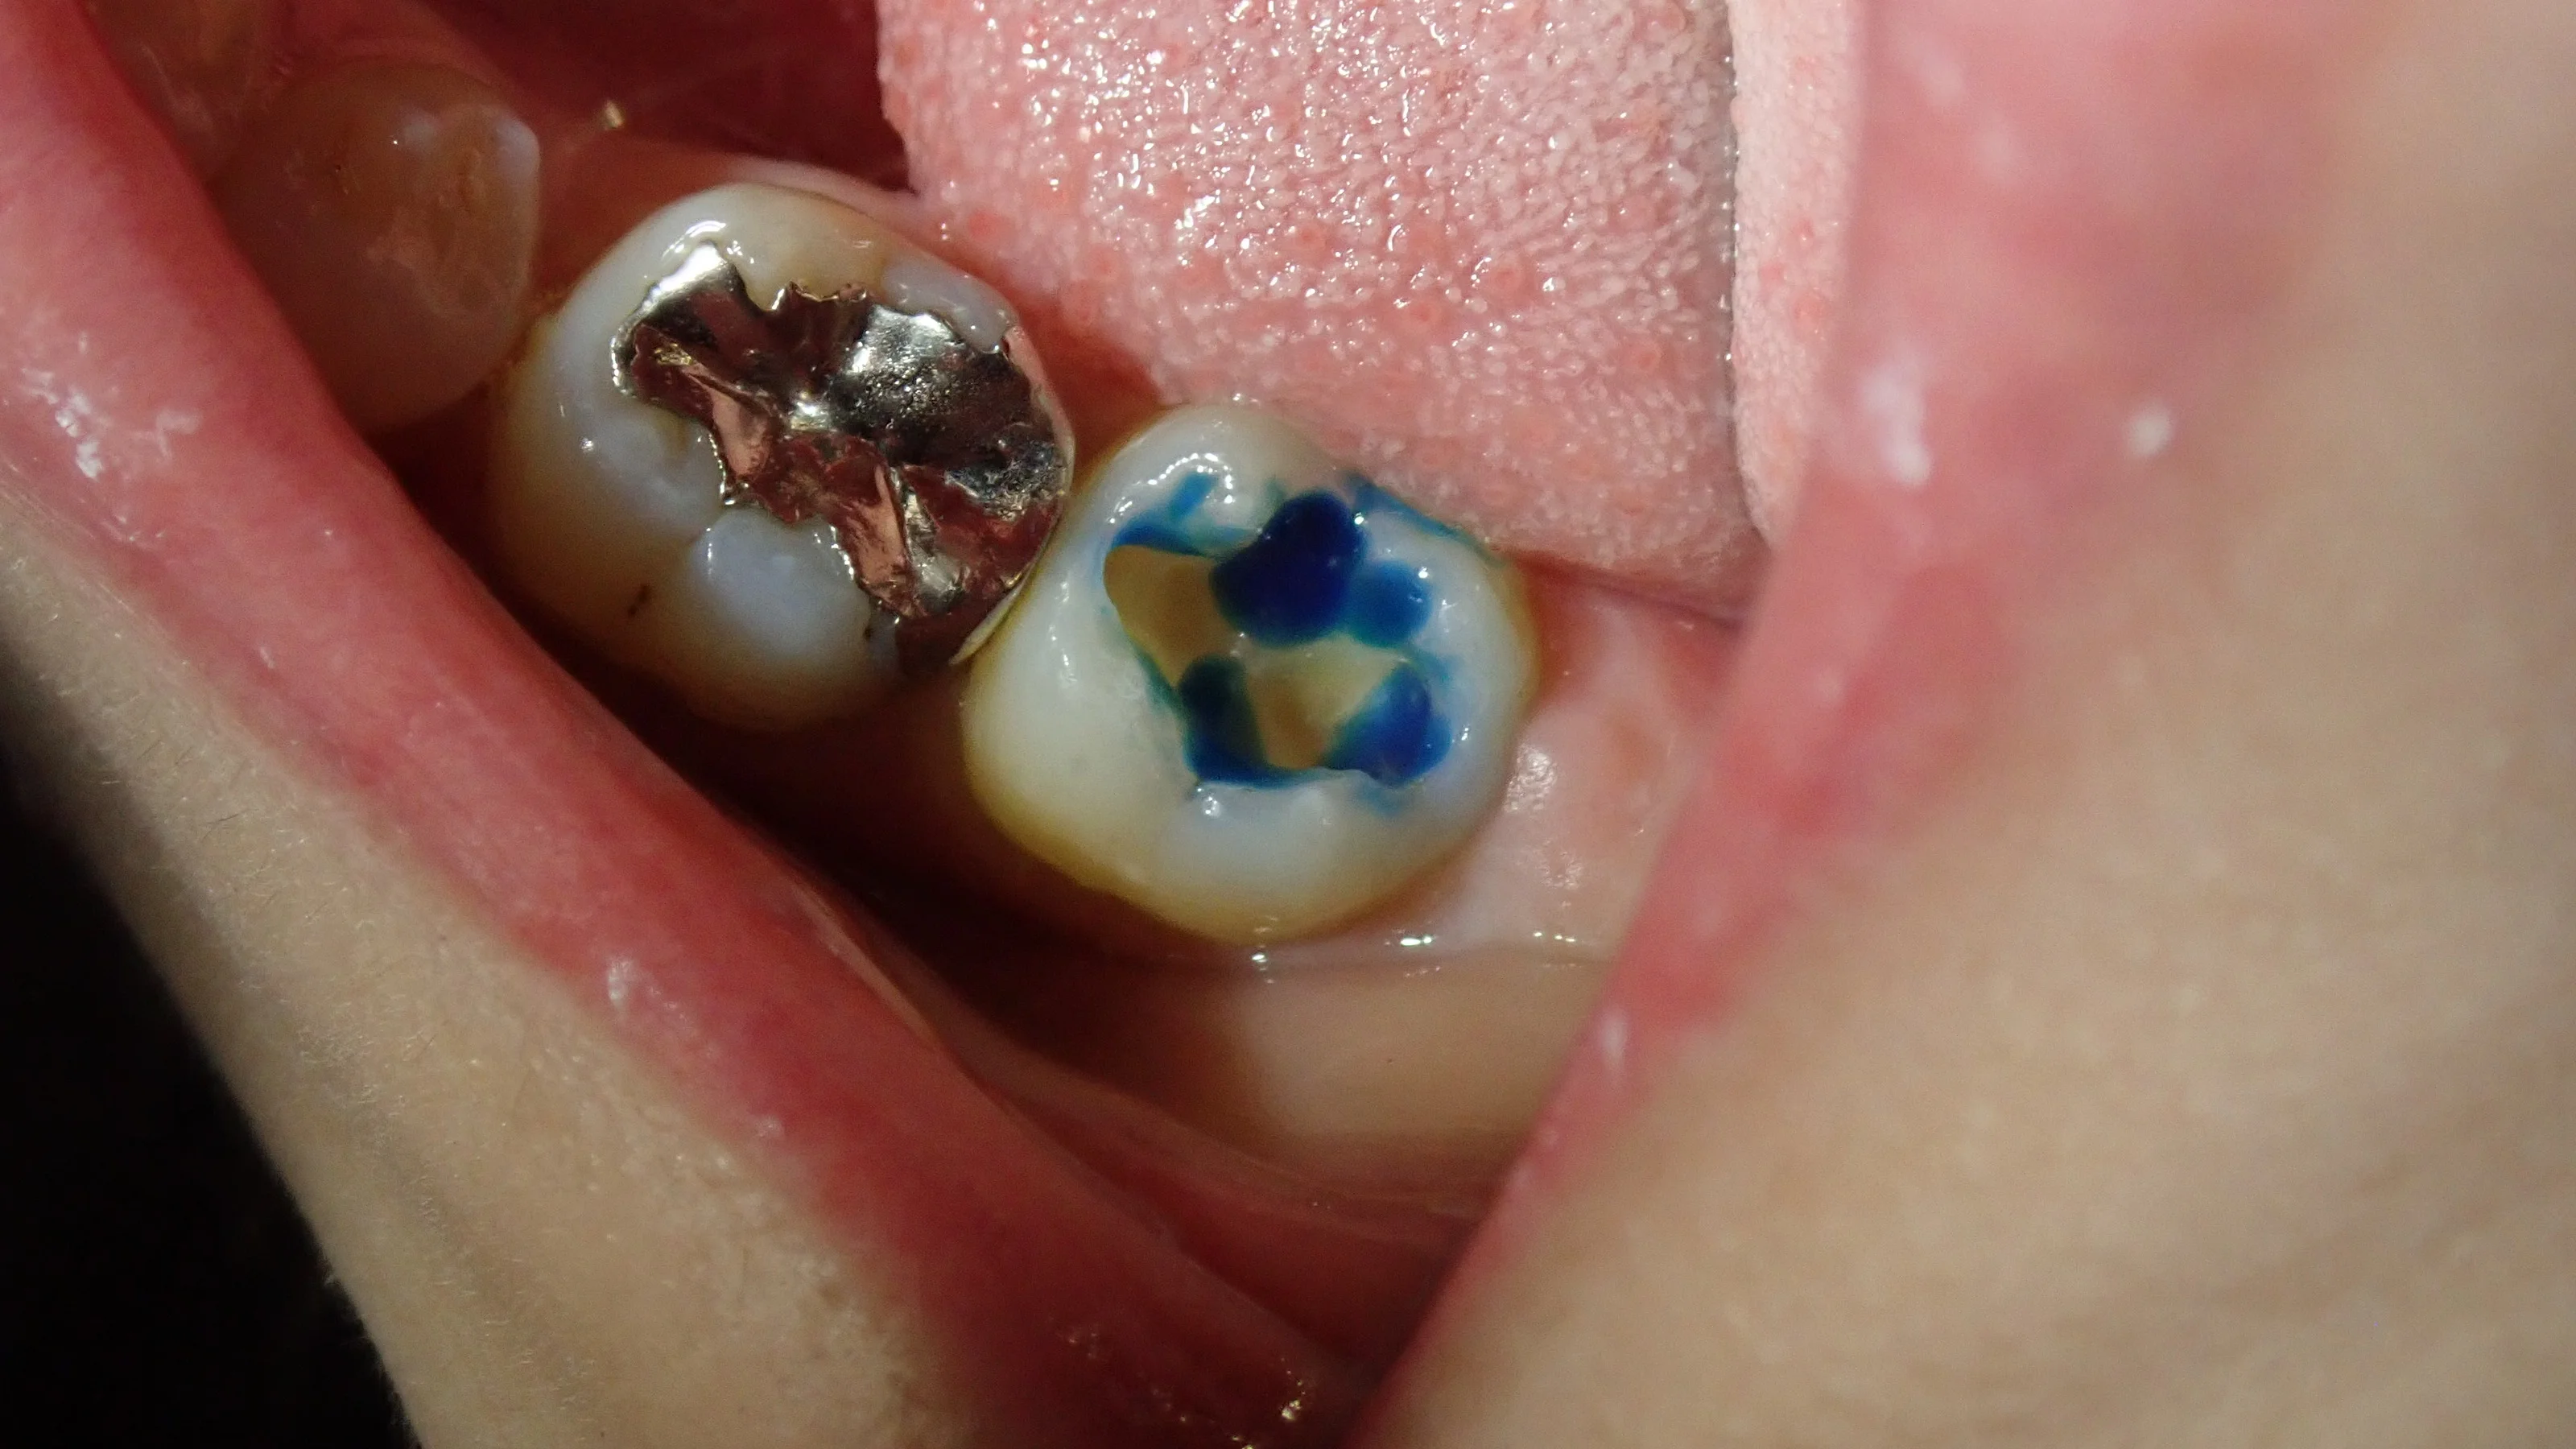

歯の表面処理をしている時に気付いてそこから取りました。

なので、

詰める前。

奥2本のダイレクトボンディング|坂寄歯科医院(取手市藤代) - 画像2